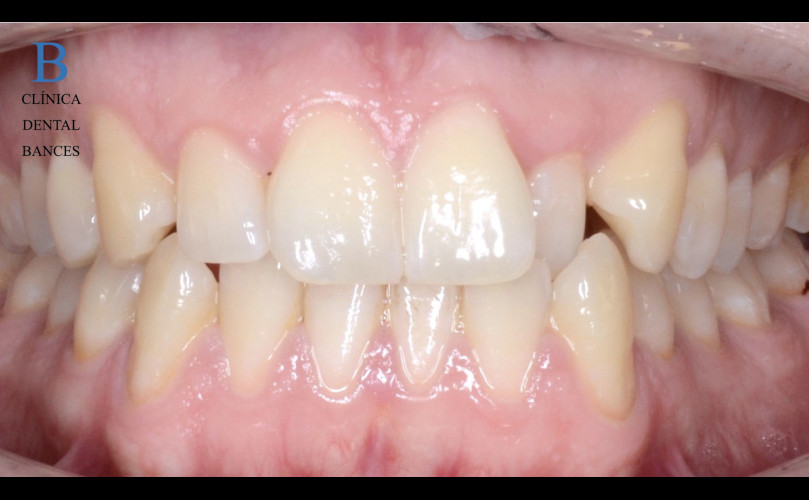

Caso de Ortodoncia con Brackts

La ortodoncia no es estética. La ortodoncia es sinónimo de salud. En ocasiones existe tanta falta de espacio que el apiñamiento impide realizar una...